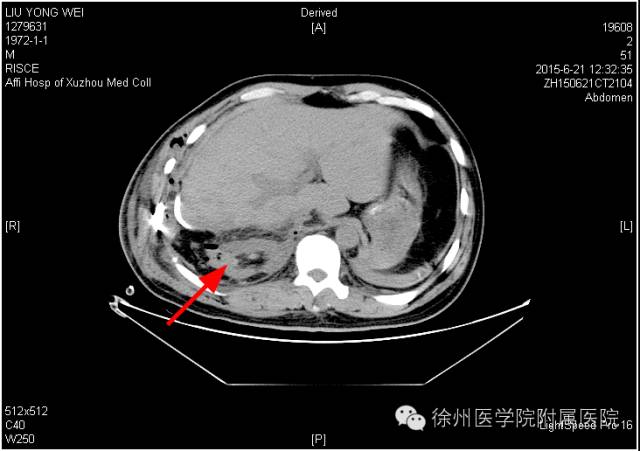

该声明称,患者手术时间是2015年6月20日,术后分别于2015年6月21日(术后第1天)和6月25日(术后第5天)的2次CT复查均显示该患者的右肾存在。

该声明还专门张贴了两张CT复查图。

图一2015年6月21日(术后第1天)CT,右肾如箭头所示。